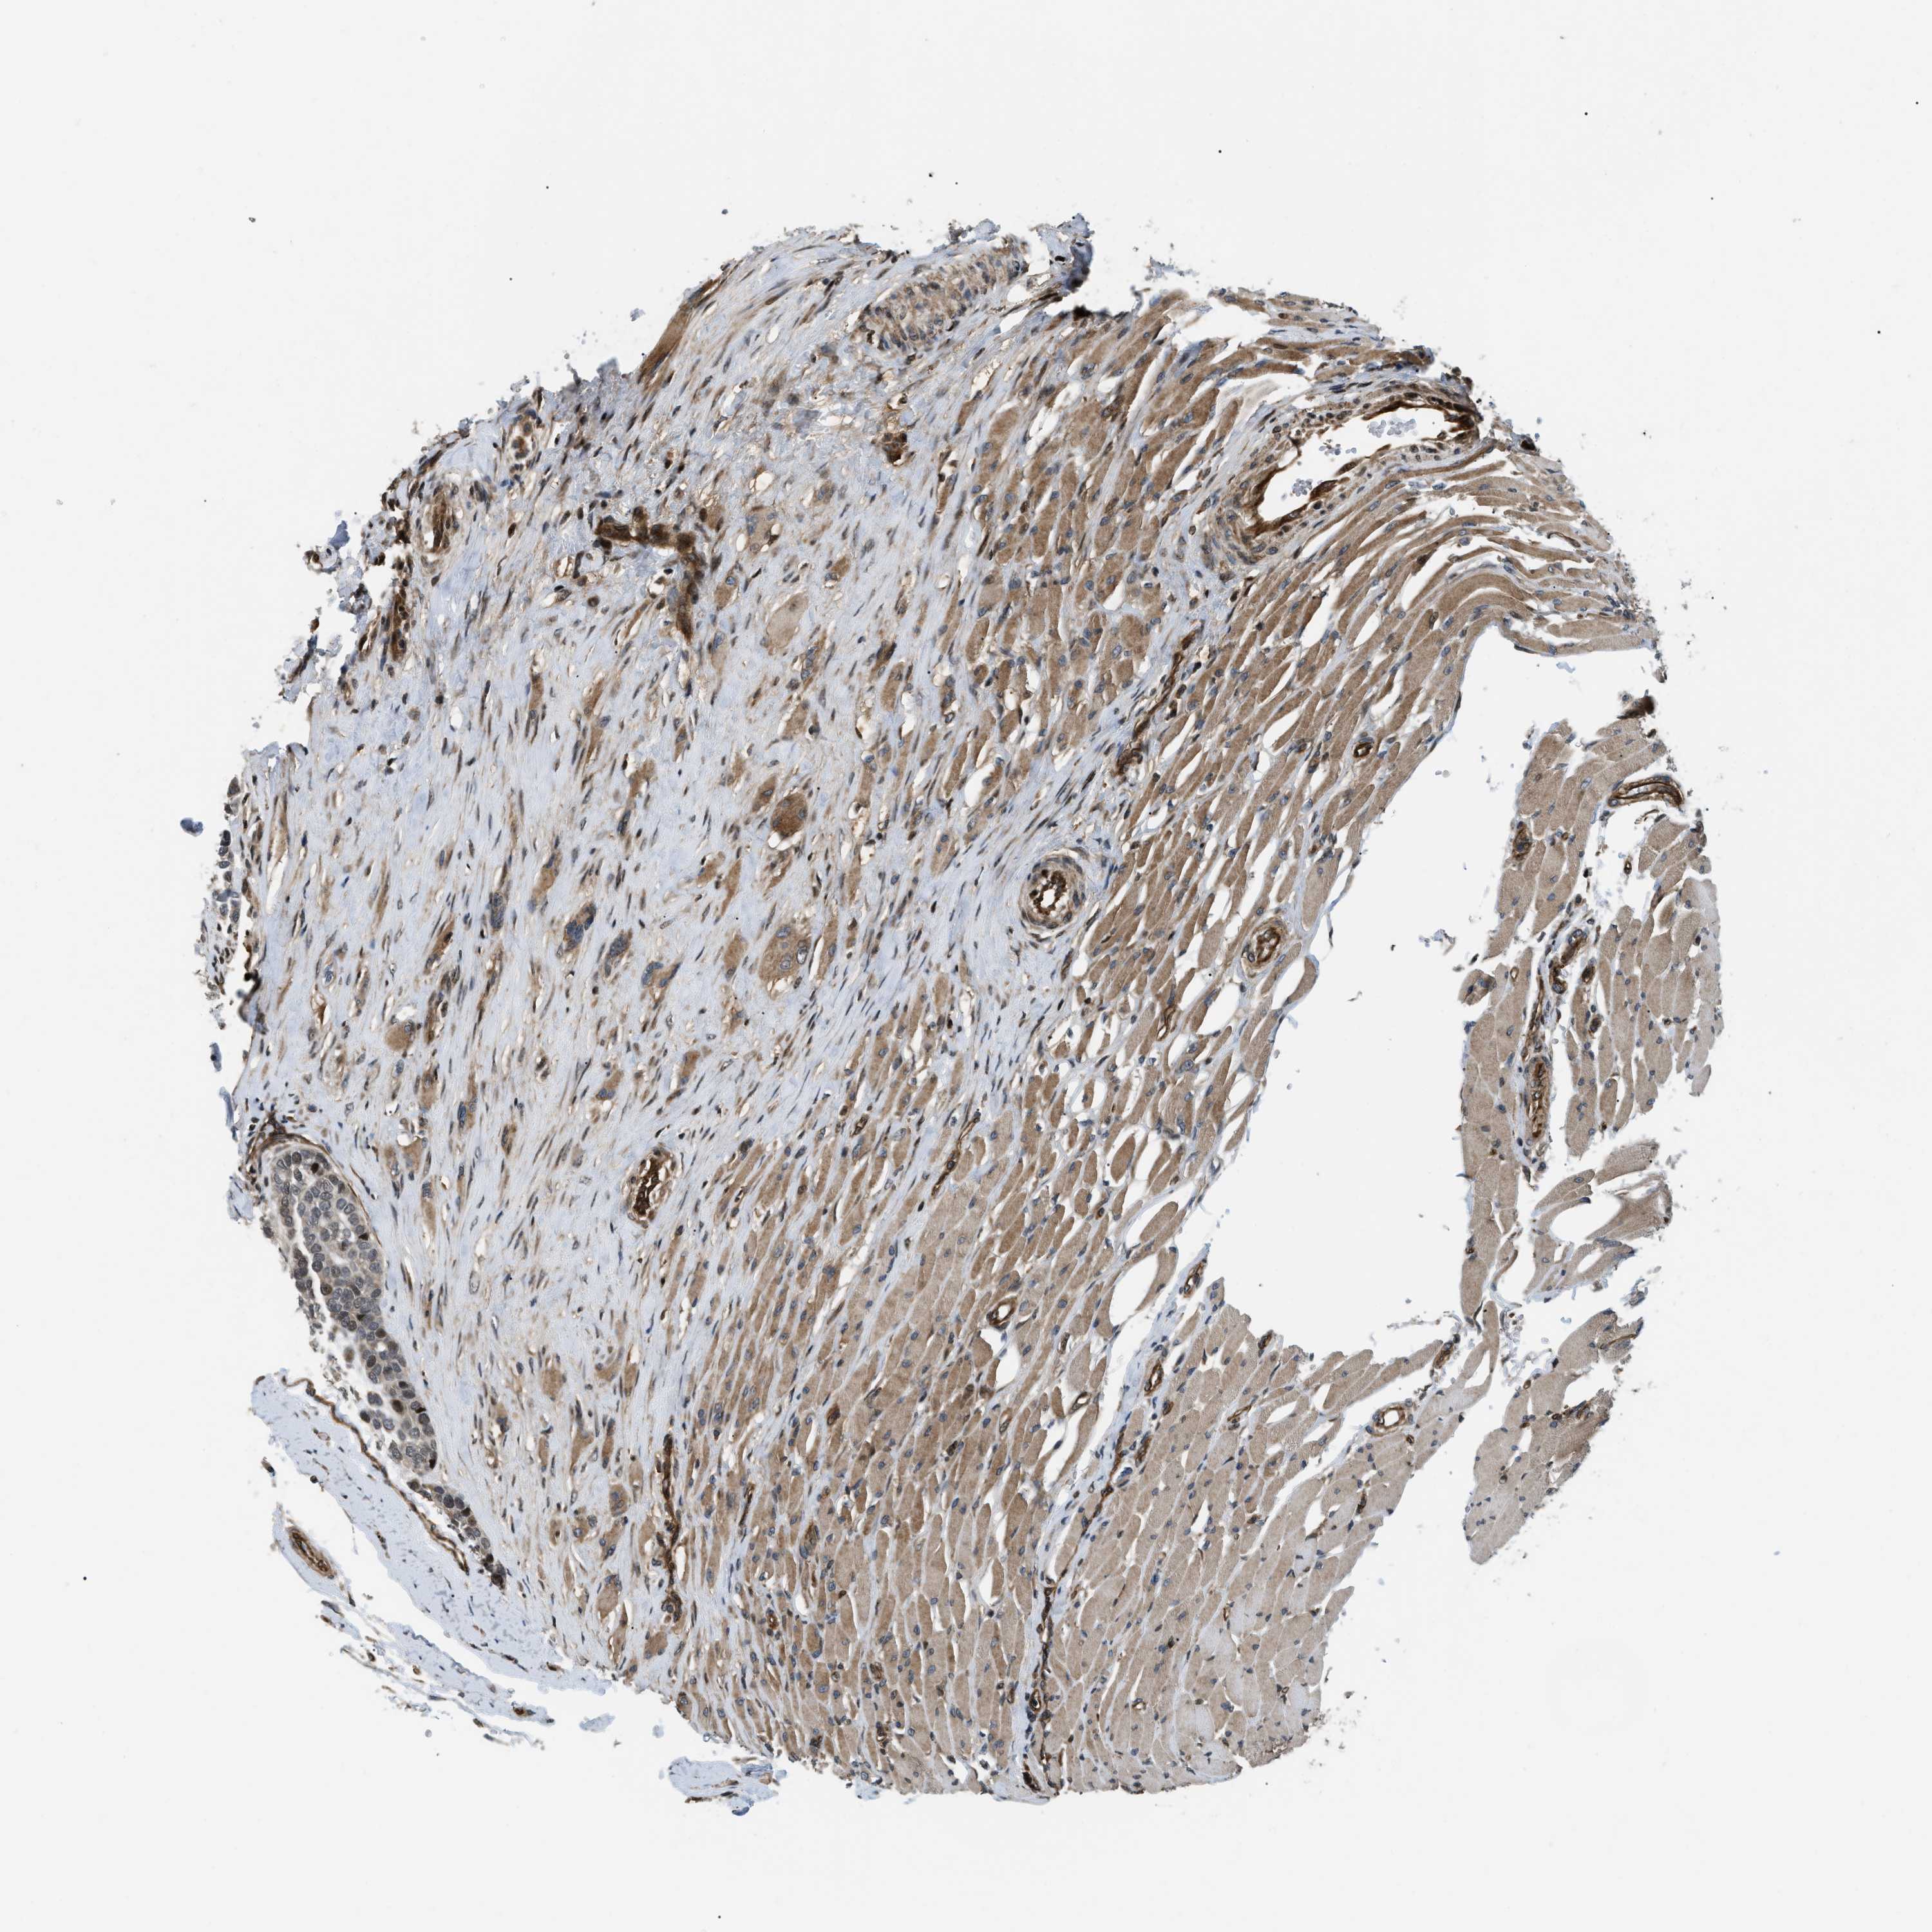

HEAD AND NECK CANCER - Protein expressioni

A mouse-over function shows sample information and annotation data. Click on an image to view it in a full screen mode. Samples can be filtered based on level of antibody staining by selecting one or several of the following categories: high, medium, low and not detected. The assay and annotation is described here.

Antibody stainingi

Antibody staining in the annotated cell types in the current human tissue is reported as not detected, low, medium, or high, based on conventional immunohistochemistry profiling in selected tissues. This score is based on the combination of the staining intensity and fraction of stained cells.

Each image is clickable and will lead to virtual microscopy that enables deeper exploration of all samples and also displays staining intensity scores, fraction scores and subcellular localization as well as patient and tissue information for each sample.

Antibody HPA017017

Squamous cell carcinoma, metastatic, NOS